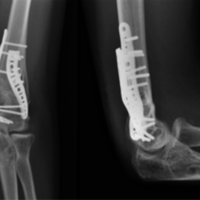

A pelvic binder was placed to decrease intrapelvic hemorrhage and repeat plain films demonstrated acceptable closure of his pelvic diastasis (Fig. 1b). After binder application and the placement of two large-bore intravenous cannulas administering crystalloid isotonic solution, hemodynamic stability was achieved and the patient was deemed stable a contrast-enhanced computed tomography CT scan revealed hemoperitoneum, 1.3 cm of pubic diastasis, and a complete, midline sacral fracture through the spinal canal and posterior sacral elements extending from S1 to the coccyx (Fig. 2). To rule out urologic injury, a CT cystogram was obtained, which revealed no evidence of bladder or urethral rupture. An urgent irrigation and debridement with surgical fixation of his left open ulnar shaft fracture were performed. Great care was taken to monitor the patient’s skin condition beneath the binder to assure he did not experience any areas of skin necrosis or compromise. 2 days after hospital admission, he underwent open reduction internal fixation of the pubic diastasis using a pelvic reduction clamp and a 6-hole non-locking symphyseal plate by Pfannenstiel approach (Fig. 3).

During reduction and fixation of the anterior pelvis, intraoperative fluoroscopic assessment revealed increased widening of the midline longitudinal sacral fracture. Due to the fracture’s involvement of the posterior sacral elements and subsequent axial plane instability, fixation of the sacral fracture was deemed necessary to prevent further displacement and potential symptomatic deformity. Under fluoroscopic guidance, transsacral-transiliac guide pins were then used to insert 7.3mm fully threaded screws into the S1 and S2 body, measuring 150 mm and 140 mm, respectively. The screws were inserted posterior to the iliaccortical density so as not to injure the L5 nerve root. Using lag-screw fixation technique principles, these screws closed down the midline sacral fracture diastasis and anatomic reduction was achieved. Postoperatively, the patient was mobilized to weight bear for transfers. At 10 weeks, he began weight-bearing as tolerated. The patient developed post-operative urinary retention and a Foleycatheter remained in place on hospital discharge. The urology team followed him as an outpatient and the catheter was removed at 1 month, at which time he was able to pass urine normally. The patient received routine follow-up evaluations. Sacral fracture union was evident at 5 months with only mild loss of reduction at the pubic symphysis (1.3 cm of diastasis) (Fig. 4). He had persistent impotence with otherwise normal urologic function and no neurologic deficits.